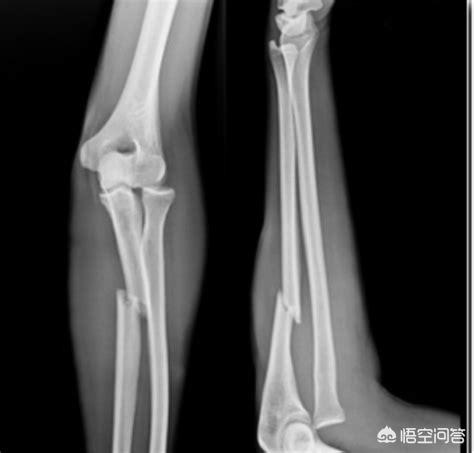

しかし、価格が高いからといって、必ずしも鮮明な画像が得られるとは限りません。骨折の場合、MRIよりもX線検査の方がはるかに鮮明であり、どの検査を選択するかは患者の具体的な状況によります!次のX線フィルムを見てください、これが骨折であることがわかります!